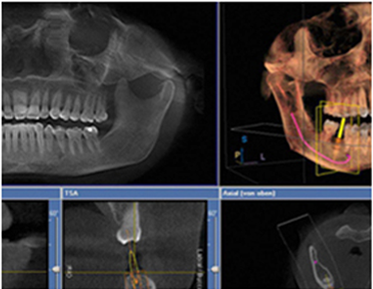

| 1 | 3D-CT 컴퓨터 분석을 통한 오차 없는 3차원 진단 |

컴퓨터 분석을 통해 보다 빠르고 면밀하게

임플란트를 식립할 수 있습니다.

| 01 | 3D-CT 컴퓨터 분석을 통한 오차없는 3차원 진단 |